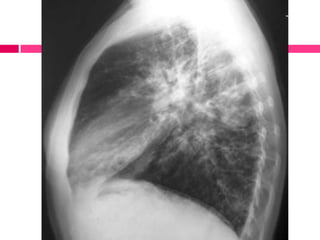

El documento describe las bronquiectasias, caracterizadas por bronquios dilatados con secreciones mucopurulentas y un cuadro clínico que incluye tos crónica y dificultad para respirar. Se mencionan diferentes tipos de bronquiectasias y condiciones asociadas, como fibrosis quística y trastornos autoinmunes. El diagnóstico incluye evaluación clínica y radiografía, con un enfoque en el tratamiento de las exacerbaciones y la eliminación de secreciones.